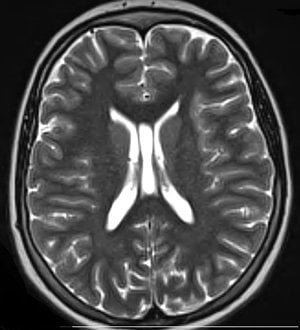

Image Source: The image is credited to Washington University at St. Louis and is adapted from the press release.